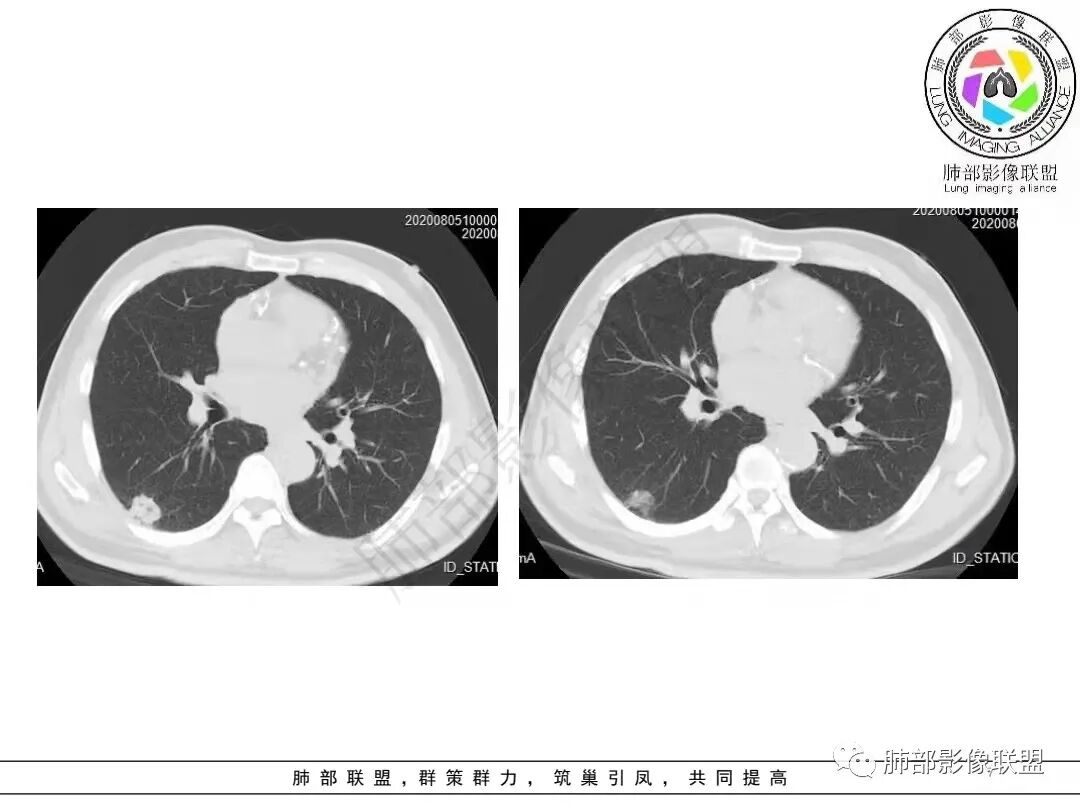

01病例资料

病例一

病例二

1.病例一:68岁男性,体检发现肺结节,肿瘤标志物CA199、CA50、CEA升高,其中CEA升高显著,超过正常范围的5倍以上。右肺下叶胸膜下结节影,整体较膨隆,部分层面可见锯齿状边缘,边界清晰,周围可见细毛细影,可见血管集束征、胸膜牵拉。密度不均,可见磨玻璃密度区及空泡征,胸膜下脂肪间隙显示不清。增强后显示轻、中度强化。

2.病例二:30岁女性,发现病灶6个月前有咳嗽咳痰及治疗史,肿瘤标志物阴性。左肺下叶胸膜下结节影,整体较膨隆,局部边缘较平直,可见毛刺,同样可见磨玻璃密度区,病灶内可见空泡征,周围可见细小毛刺及多发棘突影,同样外围病灶支气管情况难以判断。邻近肺组织内可见多发微小结节影。病灶张力不高,未见分叶及胸膜牵拉,由于纵隔窗图像太少,不宜判断胸膜下脂肪间隙有无受累,可疑胸膜下有微量积液。